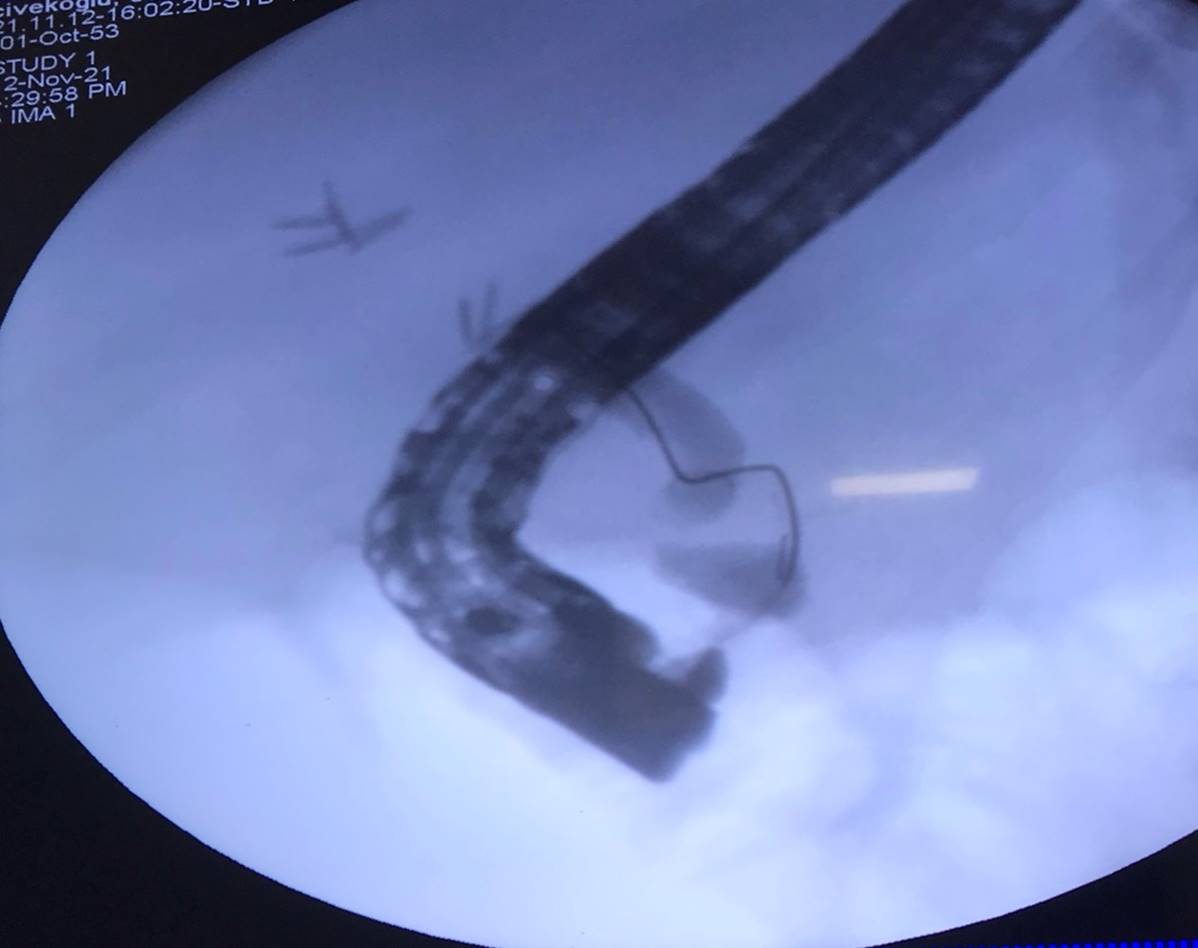

Ameliyathanede genel anestezi altında gerçekleştirdikleri işlemde; ekipteki safra yolları konusunda deneyimli cerrah Dr. Öğr. Üyesi Mehmet Fuat Çetin, laparoskopi yöntemiyle önceki ameliyatta konulmuş olan metal dikişleri çıkardı. Daha sonra gastroenteroloji uzmanları Doç. Dr. Serkan Torun ve Dr. Öğretim Üyesi Salih Tokmak’ın endoskopla safra kanalının ince bağırsağa aktığı delilikten batın içine karaciğer altına yönlendirdikleri kılavuz tel, cerrahi ekip tarafından tutularak karaciğerin içine gönderildi. Daha sonra Öğretim Üyeleri, bu kılavuz tel ve hareketli röntgen vasıtasıyla ana safra damarında kesilerek çıkarılmış olan kısmın bütünlüğünü sağlayacak şekilde stent yerleştirdi.

Hastanın sağlık durumu hakkında bilgi veren Doç. Dr. Serkan Torun, “Operasyonu başarılı geçen hasta sorunsuz bir şekilde birkaç gün sonra taburcu edildi. Haftada en az bir kez hasta ile telefonda görüşüldü, 2 haftada bir ise laboratuvar testlerini yaptırarak bize mail attı; hiç bir sorun görünmüyordu. 2 ay sonra hastanemize kontrole geldi; şikayeti yoktu. Hasta ERCP işlemine alınarak önceki stent daha büyüğü ile değiştirildi. 2 ay sonra (bu hafta) tekrar kontrole gelen hastamızın şikayeti yoktu, görüntüleme ve laboratuvar testleri normaldi.” dedi.